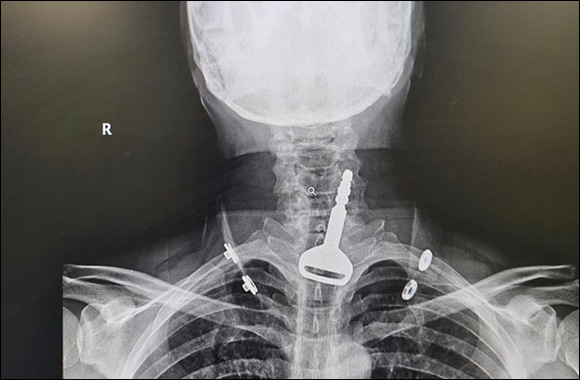

Riyadh:  A medical team in Al-Qunfudah (western Saudi Arabia) succeeded in extracting a car key from the respiratory tract of a male patient -who almost lost his life- in a quick endoscopic operation that took 15 minutes.

Saudi Health confirmed that medical teams were able on Tuesday, July 11, to save the life of a 49-year-old patient who arrived at the emergency department suffering from a blockage in his airway, where, after a clinical examination and X-rays, it turned out that a car key was stuck in the trachea.

The patient, who admitted to doctors that he was playing with the key in his mouth, accidentally swallowed it, causing partial suffocation, which required surgical intervention by laparoscopy to extract the metal object.